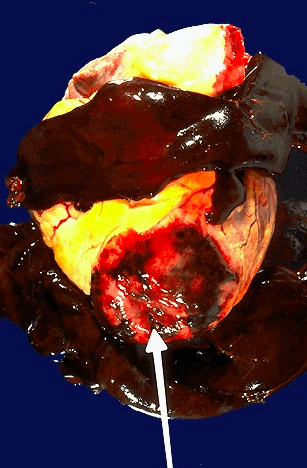

- One complication of a transmural MI is rupture of the myocardium. This is most likely to occur in the first week between 3 to 5 days following the initial event, when the myocardium is the softest

- White arrow marks the point of rupture in this anterior-inferior myocardial infarction of the left ventricular free wall and septum

- Note dark red blood clot forming hemopericardium. The hemopericardium can lead to tamponade